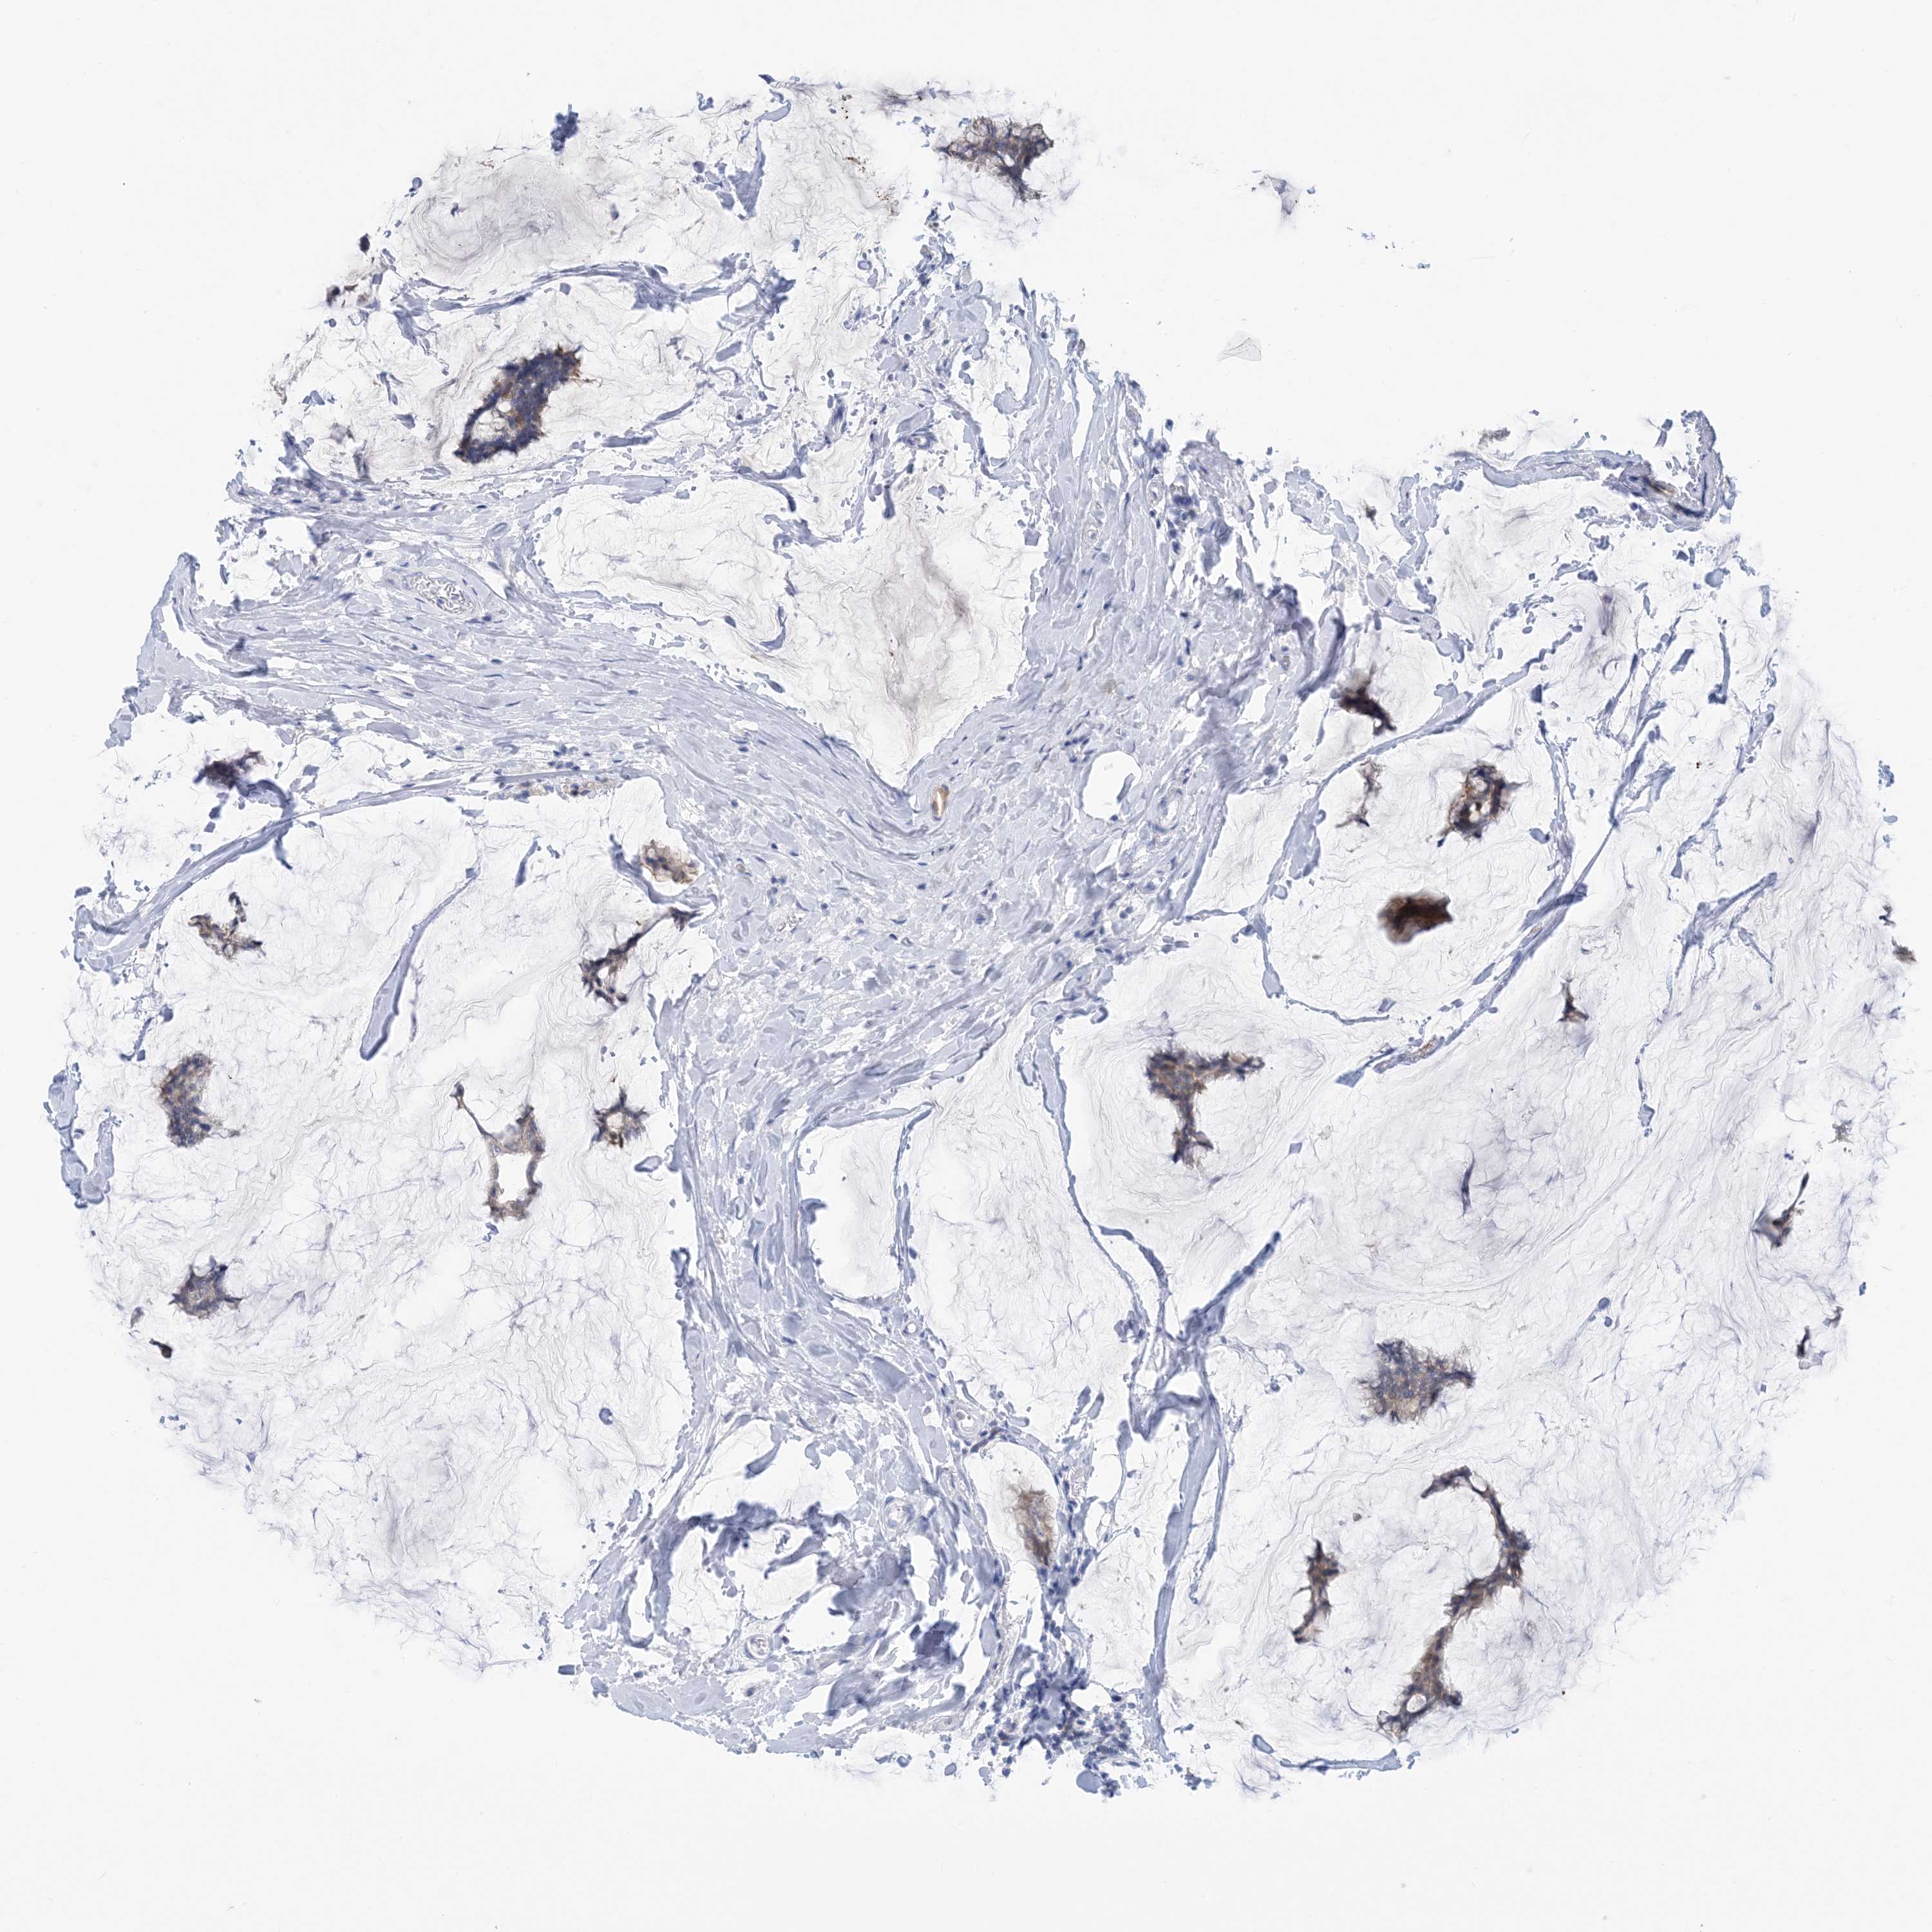

CANCER BREAST CANCER Show tissue menu

Breast cancer

Human cancer